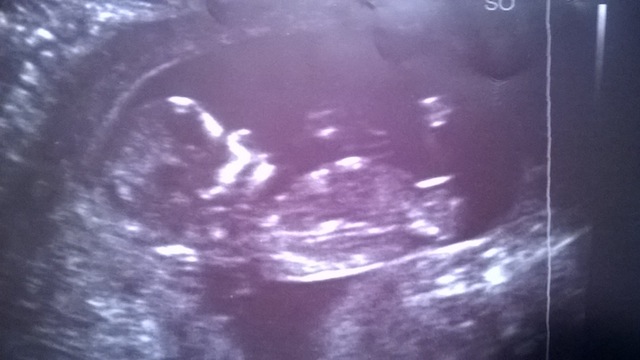

Now, today, my wife is 19 weeks. We went in for her anatomy scan of the baby, the tech got a shot of the genitals and she said based on what she sees, she thinks it's a girl because she said the lips of the labia are present in these pics below:

Attachment 19081

For those who might be confused about the "position" of the baby in those pics, it has its legs up in the air and you are seeing a closeup of the genital region.

Before we left, we asked again "So it's confirmed girl?", the tech said "Based on what I see, yes, these things are never 100%, generally speaking, but I would not say what it is if I wasn't confident about it".